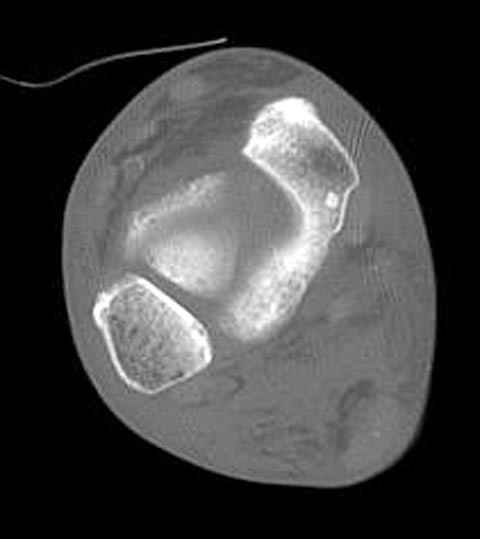

Уважаемые участники русского Ортофорума, поздравляю всех со всеми прошедшими праздниками: Новым годом, Рождеством, Hanukkah, Kwanzaa, желаю участникам всего наилучшего и здоровья.Повреждение таранной кости.Больной 81г автоавария, повреждение таранной кости, здесь снимки.

Вдогонку по поводу перелома таранной кости, больная 81, не страдает диабетом, перелом закрытый, в первый же день поступления ограничились временным наружным фиксатором (как на снимке).

За пару недель насчитал 5 больных с переломом таранной кости, из них двое с двусторонним повреждением.